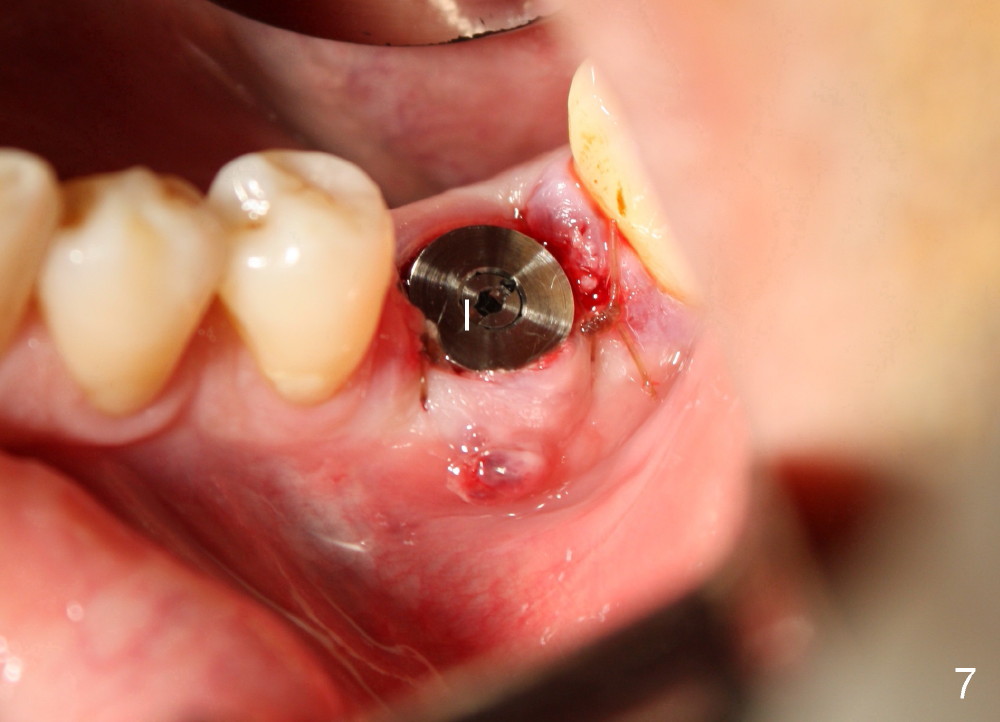

A 41-year-old man has discomfort in the lower left 1st molar. Exam shows swelling and a fistula in the mesiobuccal gingiva (Fig.1 >) and large radiolucency around the mesial root (Fig.2 *). After extraction and thorough debridement, osteotomy is initiated in the mesial socket, but the upper portion of the reamer (Fig.3 R, 2.5 mm) is placed in the middle of the edentulous space. By the time 5 mm reamer is removed, the osteotomy (Fig.4 O) forms mainly in the mesial socket with the septum (S) deviated to the distal socket. A 7x17 mm tap is placed with stability (Fig.5 T). An implant with the same dimension is placed with insertion torque more than 60 Ncm (Fig.6 I). With the large implant, two proximal sutures are able to close the remaining socket gaps (Fig.7). The swelling and fistula disappears and the gingiva tightly surrounds the implant in 1 week postop (Fig.8).